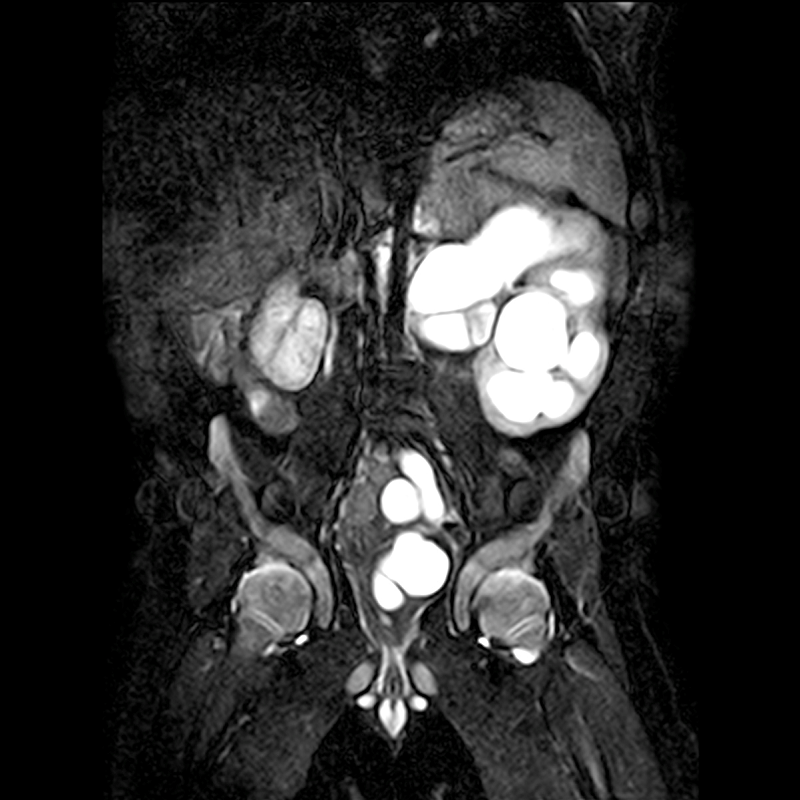

Aufnahmen einer Uro-MRT bei einem vier Monate alten Kind mit einer Doppelniere links mit sogenannten Megauretheren (erweiterten Harnleitern). Die linke Niere ist unauffällig.

Dr. Latta: Der Kinder- oder Hausarzt stellt meist mittels Ultraschall Auffälligkeiten fest und überweist seinen Patienten in das Clementine Kinderhospital oder in die Klinik für Neugeborenen- und Kinderchirurgie und -urologie am Bürgerhospital Frankfurt. Fragestellungen sind dabei z.B.: Warum fließt der Urin nicht richtig ab? Sind die Nieren gestaut? Ist der Funktionsanteil einer Niere zu gering? Liegt eine Doppelniere (eine Niere mit zwei Nierenbecken) vor? Mündet der Harnleiter in die Blase oder gibt es Fehlanlagen? Funktionieren beide Nieren gleich? Mit der Uro-MRT können wir uns die inneren Organe noch genauer ansehen als mit dem Ultraschall und so den ersten Verdacht bestätigen oder entkräften.